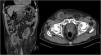

A 82-years-old man presented to the emergency room for a right inguinal pain associated with renal failure. On clinical examination, we found a voluminous non reducible bilateral inguinal hernia (Fig. 1). A computerized tomography scan (Fig. 2) found a bilateral inguinal hernia containing both orthotopic kidneys causing chronic renal failure secondary to bilateral hydronephrosis.